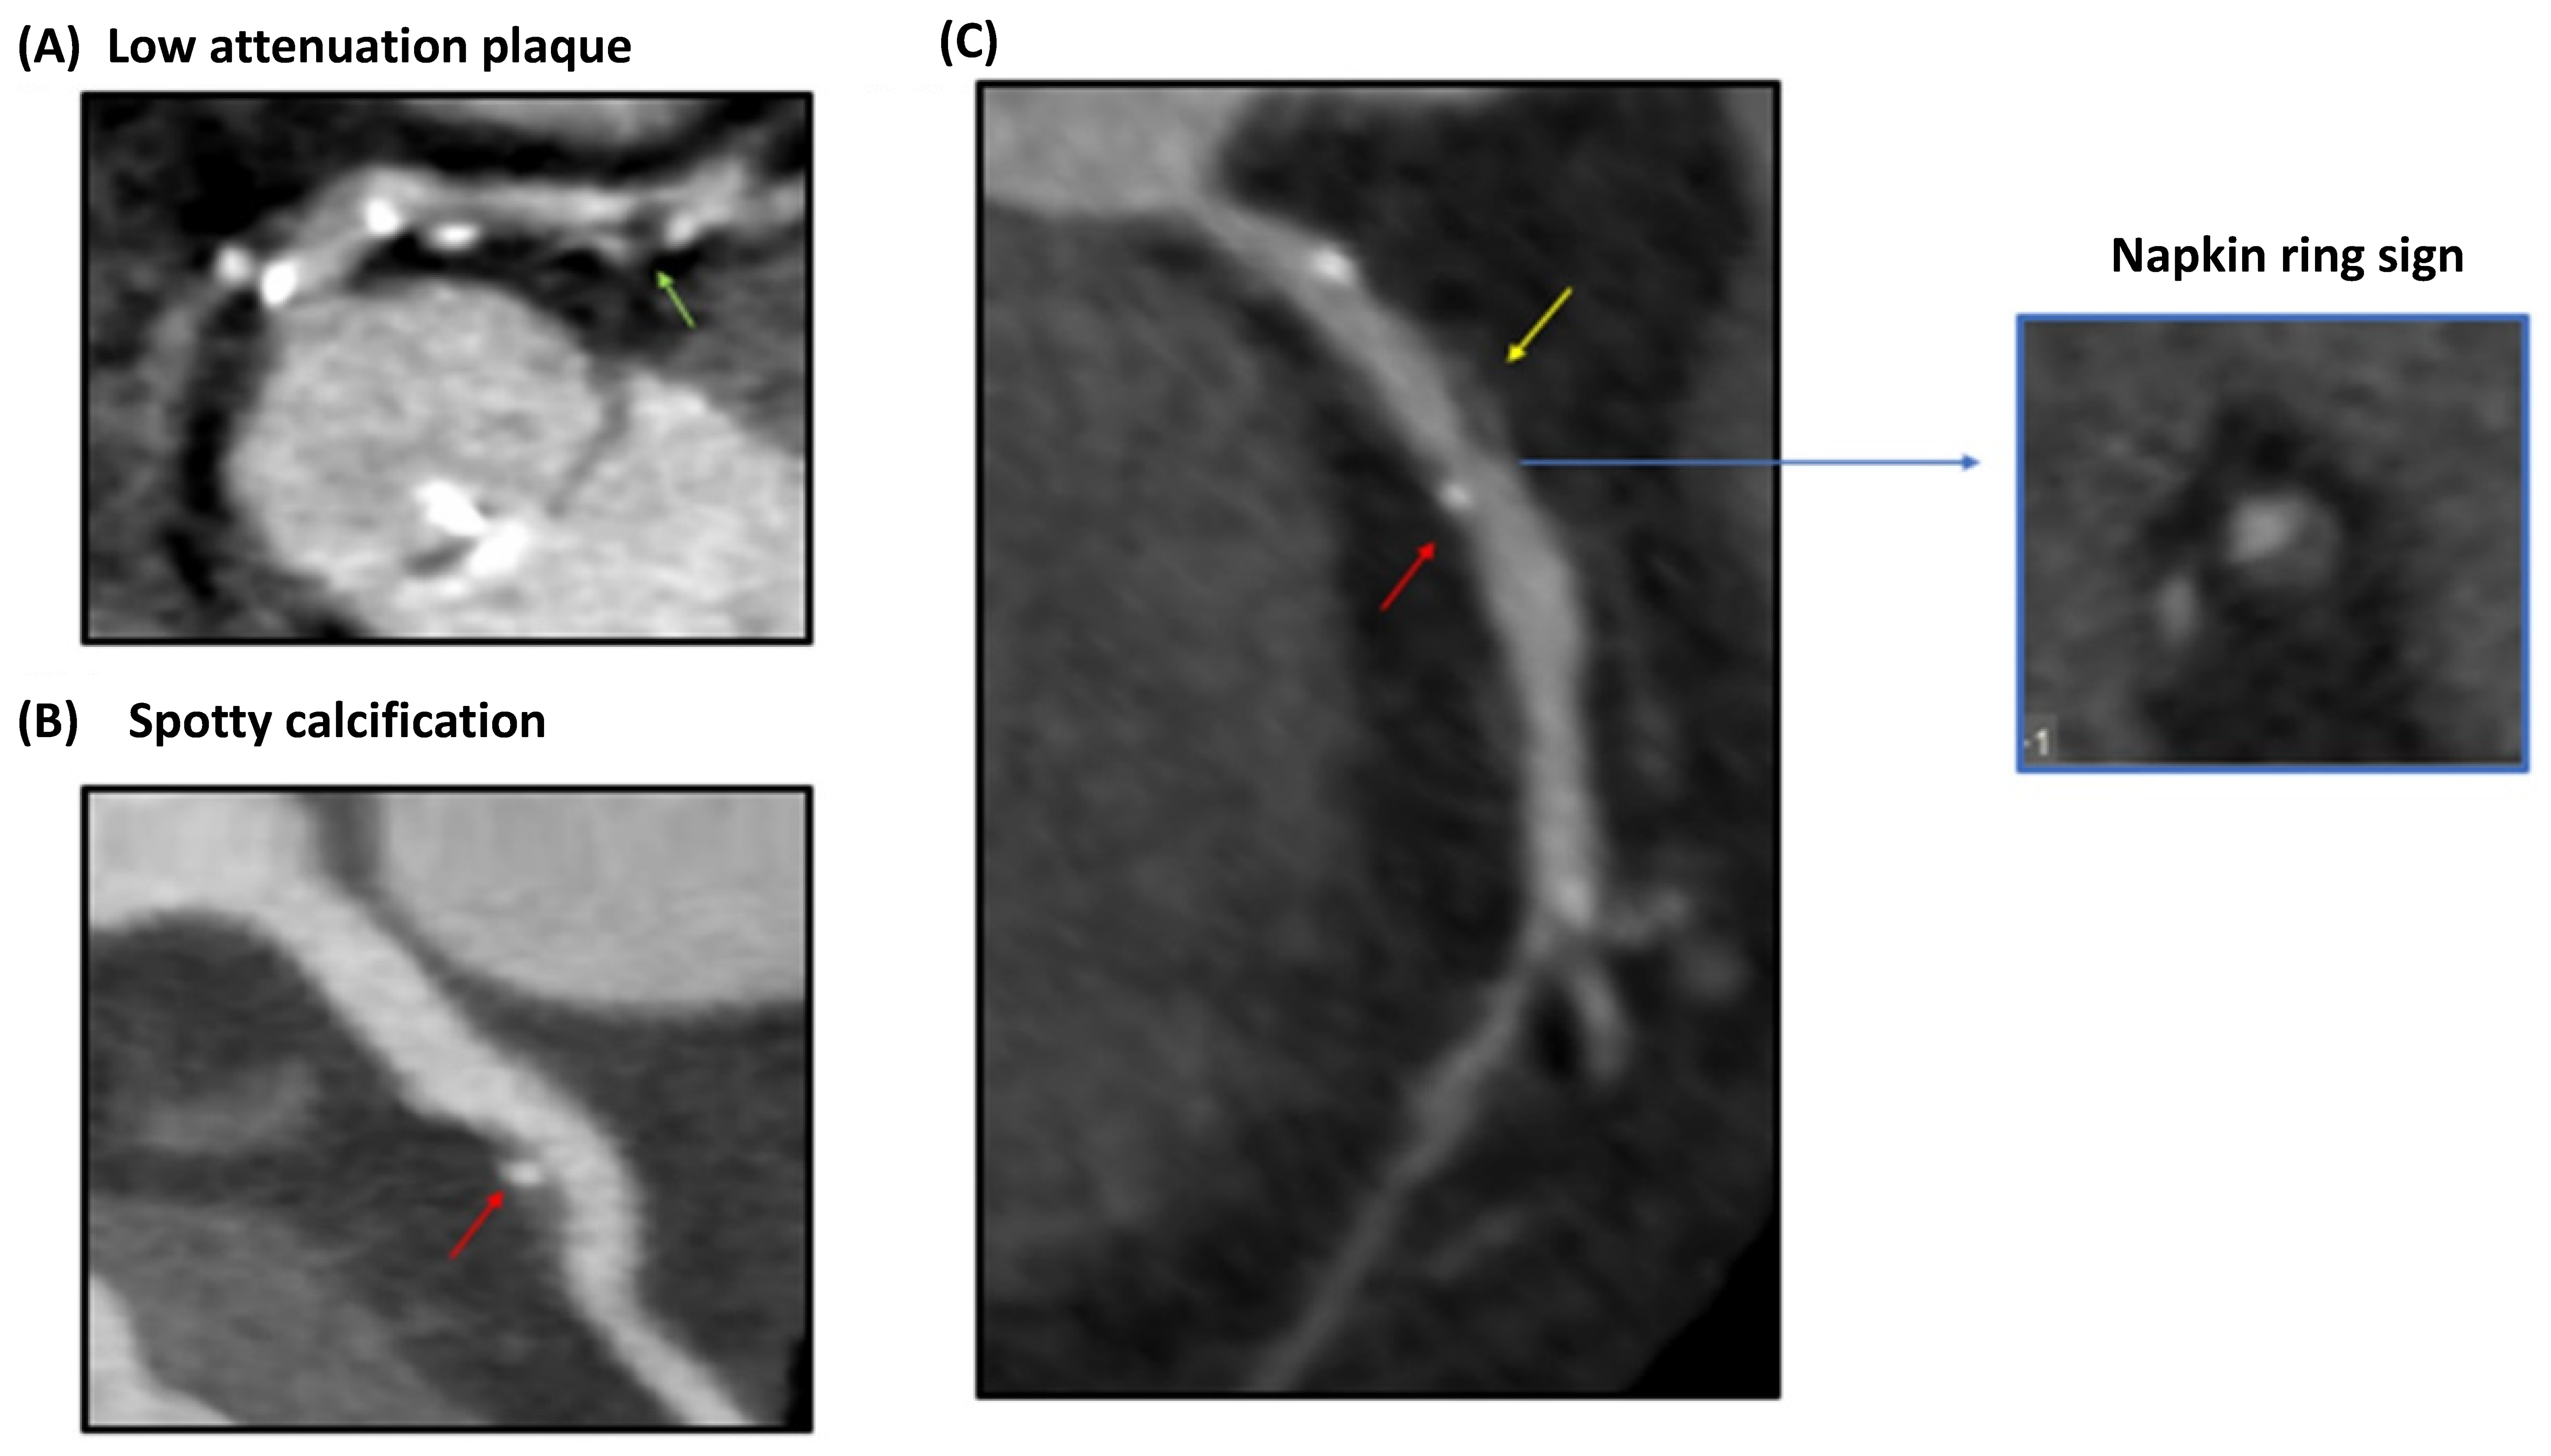

4.2. Vulnerable Plaque Assessment